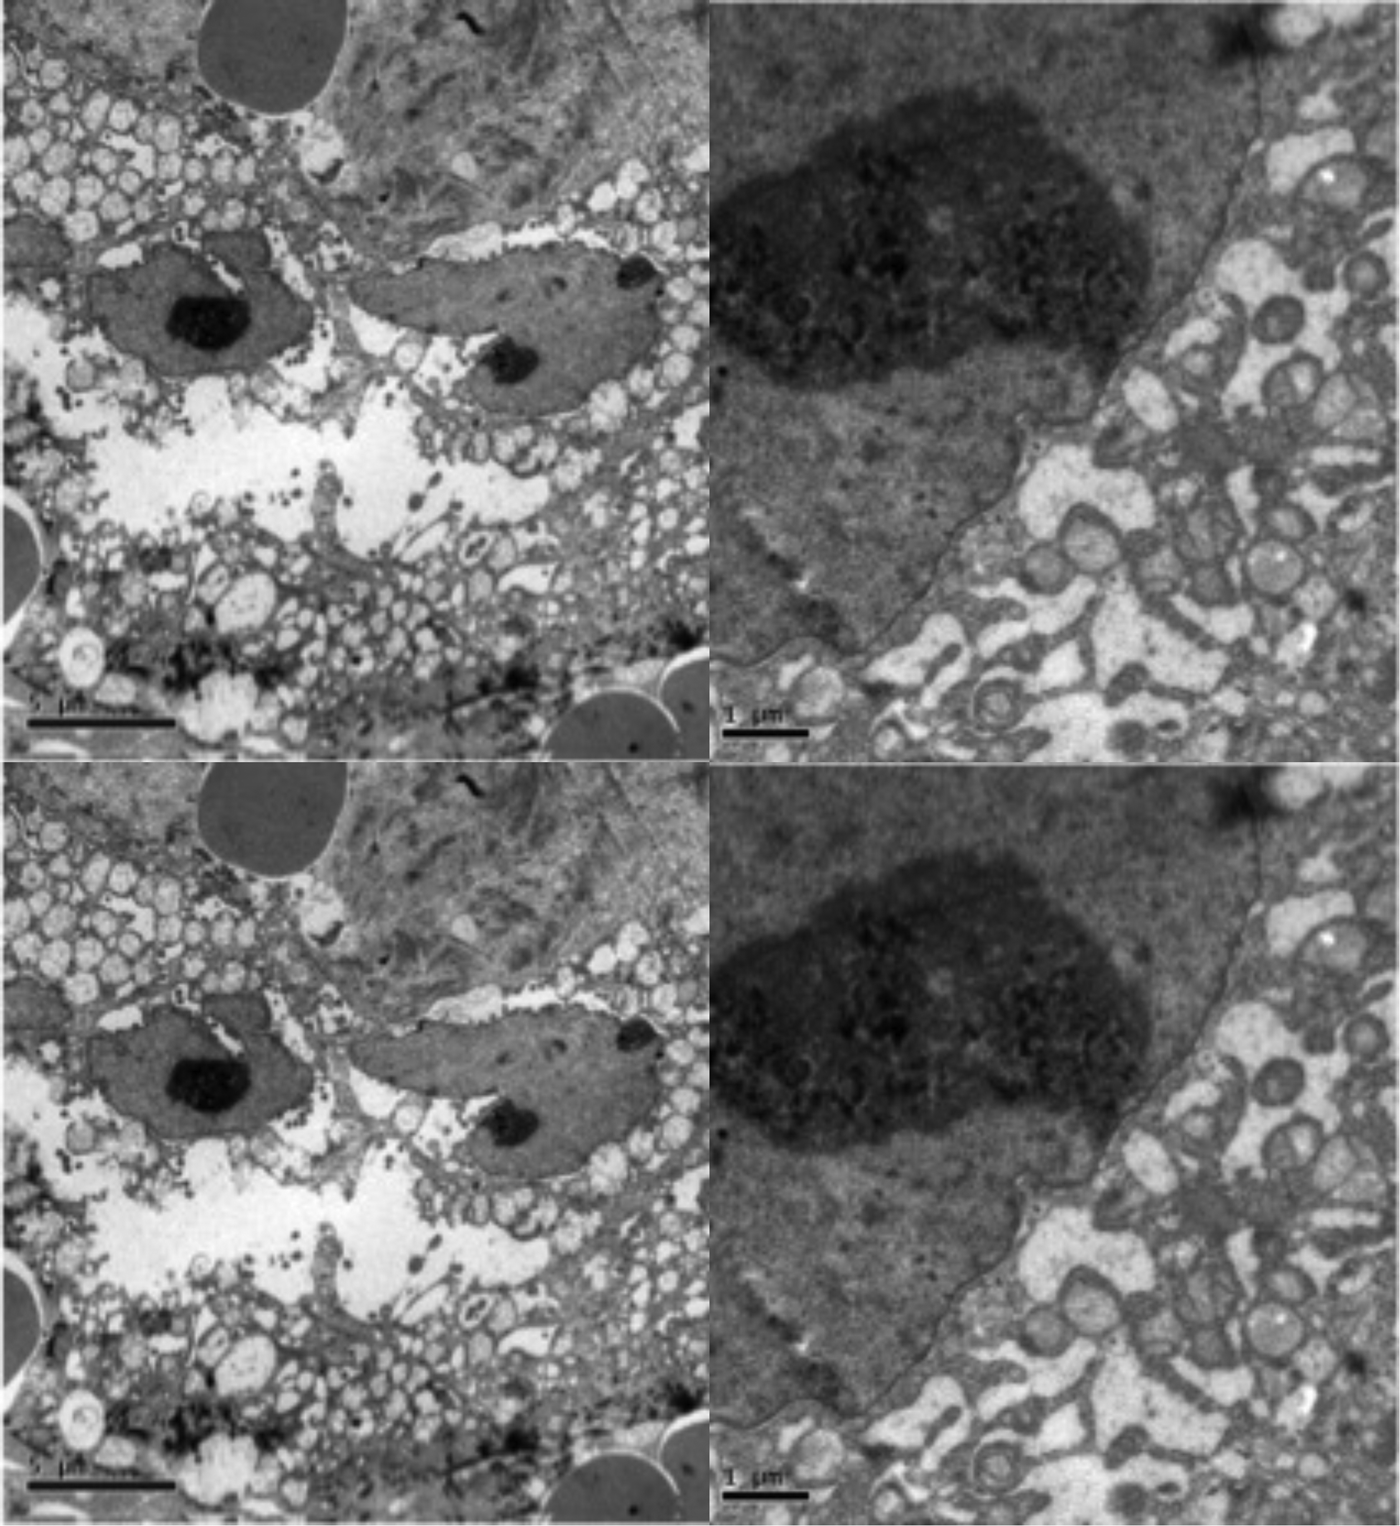

In a hypothesis-generating and exploratory experiment, we used transmission electron microscopy to evaluate mitochondrial ultrastructure in liver tumour biopsies taken from patients with HCC who had undergone LEAM RF EMF exposure (Figures 2, 3). Mitochondria appeared to congregate in cellular locations distant from microtubules, and to show morphological changes characterized by disorganized crista and swelling of the matrix. To our knowledge, these abnormalities have not been previously reported in the context of HCC. This finding needs replication in future studies, but is consistent with effects of LEAM RF EMF exposure on mitochondria.

Figure 3

Abnormal mitochondrial morphology in a patient with HCC after low-power amplitude-modulated radiofrequency electromagnetic field exposure. Tissue sections at ultrastructural level of the patient given in Figure 2 are shown. Left: HCC cell with disorganized cytoplasmic organelles and diffuse electron-lucent dilation of reticulum, probably reflecting water accumulation, and mitochondria present in dilated regions. Right: HCC cell with hydropic dilated reticulum around isolated and atypical mitochondria showing morphological changes characterized by disorganized crista and swelling of the matrix. HCC, hepatocellular carcinoma.